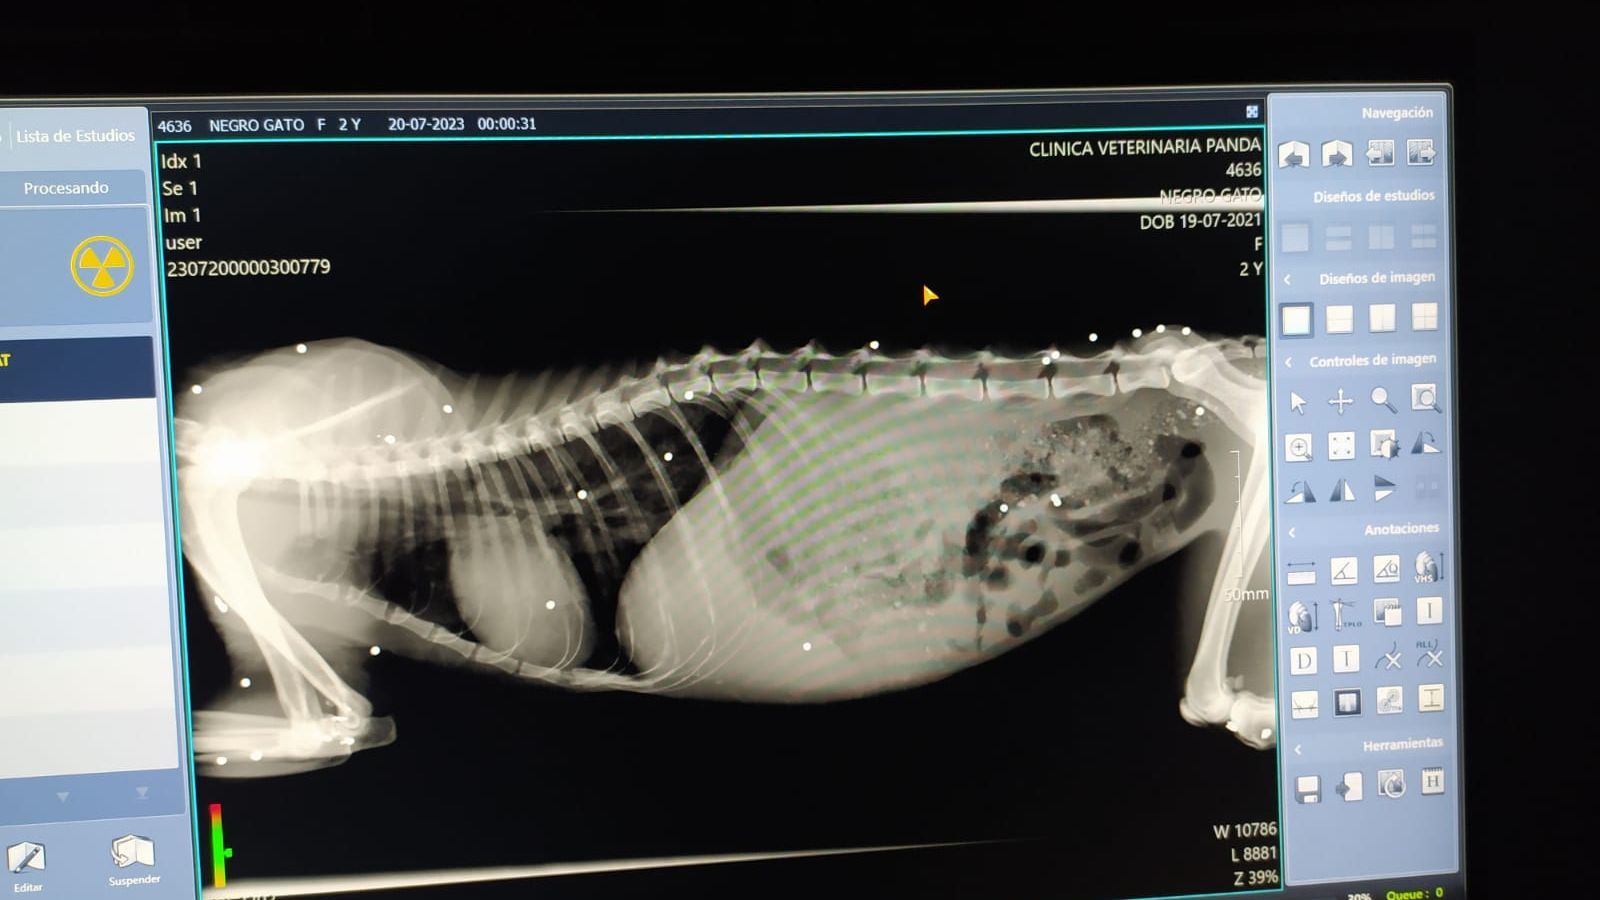

AlmeríaDuele solo mirarlo. El ácido que han vertido sobre él ha dañado su cuello, un ojo y las patas delanteras. También le han cortado la lengua y las orejas. Por si no fuera suficiente, las radiografías muestran al menos 30 perdigones incrustados en su cuerpo. A pesar de estas brutales lesiones, Kofuku, un gato feral de color negro y ojos verdes, sigue vivo.

Ahora, Kofuku permanece ingresado en una clínica veterinaria donde han confirmado la gravedad de sus lesiones. “Cuando le realizamos la radiografía nos quedamos espantados porque tenía todo su cuerpo lleno de perdigones. Cada punto blanco es uno”, lamenta el presidente de la protectora que recalca que es un gato joven, de no más de dos años. “Sus dientes de adulto están muy nuevos, así que pensad, con lo poquito que lleva vivo, ¿cómo es posible que tenga tanto maltrato?”, se pregunta.